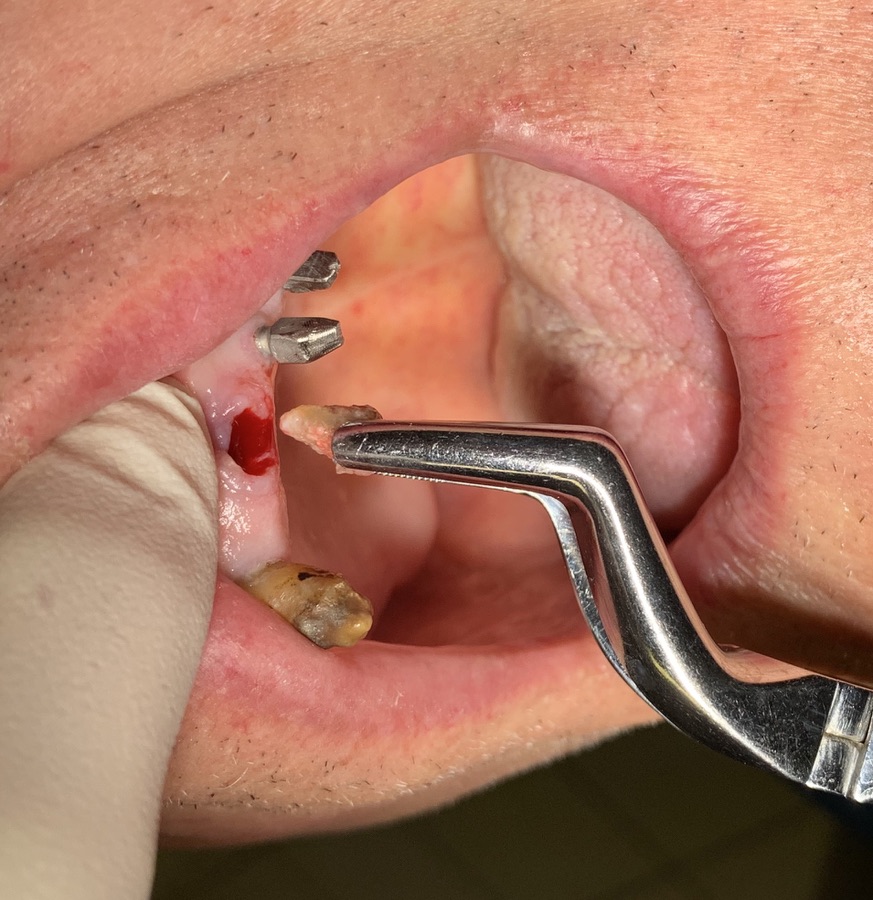

Implant type: Tramonte     No. Implants inserted: 2       Welding: No      Dental area: 21   23

Intraoral Rx app: Vix win       CT scan: No      Extraction situation: immediate post extraction implants        Density according to Misch: D2

Operator1:  Dr. Bellini     Operator 2: Dr. Bazzoli      Drill sequence: only lanceolate      Tap sequence: only diam. 4 mm.

Occlusal load: immediate     Complications: none      Video or written statement of satisfaction: video su Iophone xs.